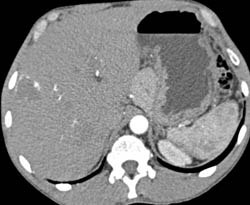

Portal Hypertension With Splenomegaly and Varices and Collaterals